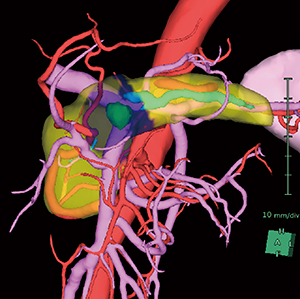

膵臓解析では,膵液の経路である膵管を自動で抽出する機能を搭載し,術前に膵管の位置を視覚的にとらえることができる。また,膵臓直交断面を表示することにより,指定位置での膵管の詳細な位置や膵実質断面の厚み,面積を計測することが可能である。加えて,ガイドライン1)で推奨されている門脈左縁での切除ラインの任意設定(図2)や,各膵腫瘍の位置に応じて腫瘍マージンを表示する機能(図3)を追加し,適切な切除ラインをプランニングするために必要な機能を提供する。切除ラインから残膵ボリューム(あるいは切除される膵臓ボリューム:図4)を算出し,体積評価も可能である。さらに,肝臓解析や腎臓解析と同様に,鏡視下シミュレータ(別途オプション必須)を連携して起動させることで,仮想内視鏡ビューを表示し,術前,術中に参照することができる(図5)。

図2 膵臓三次元画像と門脈左縁切除時のCT断面